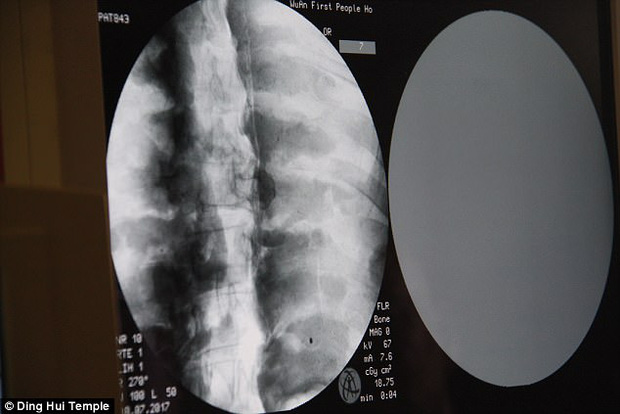

Theo tờ Daily Mail, đầu tháng 7 năm 2017, các nhà khoa đã tiến hành chụp CT để "nhìn thấu" bên trong xác ướp mạ vàng của nhà sư Ci Xian nổi tiếng Trung Quốc. Nhà sư Ci Xian được cho là một nhà sư được vạn dân kính trọng, ông đã đi từ Ấn Độ cổ đại đến Trung Quốc cổ đại để quảng bá Phật giáo.

Ngày 8/7/2017, trước sự chứng kiến của các nhà sư, giới truyền thông và nhiều người dân, các nhà khoa học đã tiến hành chụp CT xác ướp nhà sư Ci Xian.

Ban quản lý của ngôi chùa đã sắp xếp một buổi chụp CT xác ướp nhà sư Ci Xian vào ngày 8 tháng 7 năm 2017.

Mọi người đều bàng hoàng khi các bác sĩ cho biết nhà sư Ci Xian vẫn còn nguyên bộ xương, và một bộ não hoàn chỉnh. Tức xác ướp này đã được bảo quản gần như nguyên vẹn sau hơn 1.000 năm. Điều này khiến giới khoa học sửng sốt với kỹ thuật ướp xác thời bấy giờ.

Bác sĩ Wu Yongqing nói với kênh Pear Video sau khi tiến hành chụp CT cho xác ướp: "Chúng tôi có thể thấy xương của ngài ấy khỏe mạnh như một người bình thường. Hàm trên, răng trên, xương sườn, xương sống và tất cả các khớp đều vẫn nguyên vẹn. Thật không thể tin được khi thấy điều này".